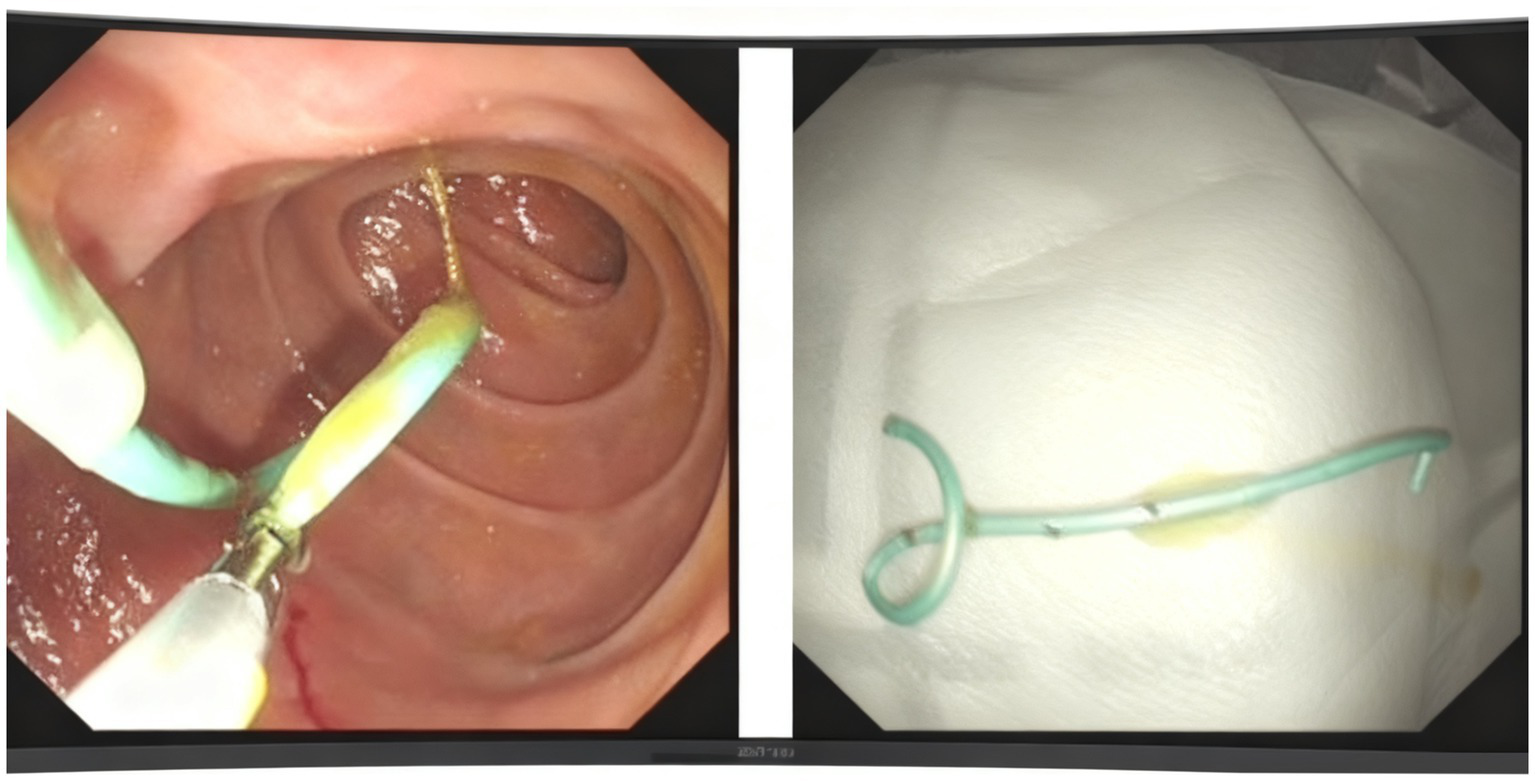

We utilized a duodenoscope to access the descending part of the duodenum, where we observed a single-hole type duodenal papilla. A three-chambered knife was employed to carry a guidewire and insert the tube, successfully entering the pancreatic duct. We maintained the guidewire in the pancreatic duct while injecting contrast agent through the three-chambered knife. This allowed us to visualize the main pancreatic duct, which measured approximately 1 cm in diameter. After the contrast injection, we aspirated the contrast agent from the pancreatic duct and placed a 5 Fr × 5 cm plastic pancreatic duct stent (Boston Scientific Jagwire™ SPSOF-5-5) in the duct. Upon stent insertion, a significant amount of white flocculent material was noted to flow out. The bile duct was not visualized during the procedure (Figure 3). Additionally, we inserted a nasojejunal nutrition tube. The patient’s vital signs remained stable upon completion of the procedure. This dual approach facilitated effective cyst decompression while simultaneously attenuating pancreatic auto-digestion by reducing secretory stimulation.

Figure 3

The process of inserting a papillary pancreatic duct stent.

After two-month follow-up, we removed the pancreatic duct stent (Figure 4). His BMI had improved at 17.56 kg/m2, findings compatible with clinical improvement. Imaging studies both in CT scan and endoscopic ultrasonography confirmed reduction in the size of his PPC (measuring 2.2 cm × 0.8 cm × 1.1 cm) and his previously mentioned elevated laboratory values were all within normal limits (Figures 1B, 2B).

Figure 4

The process of moving the stent.